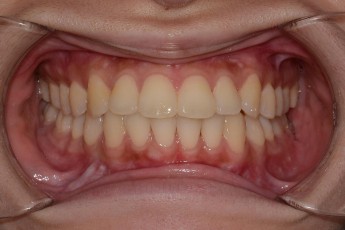

Before

After